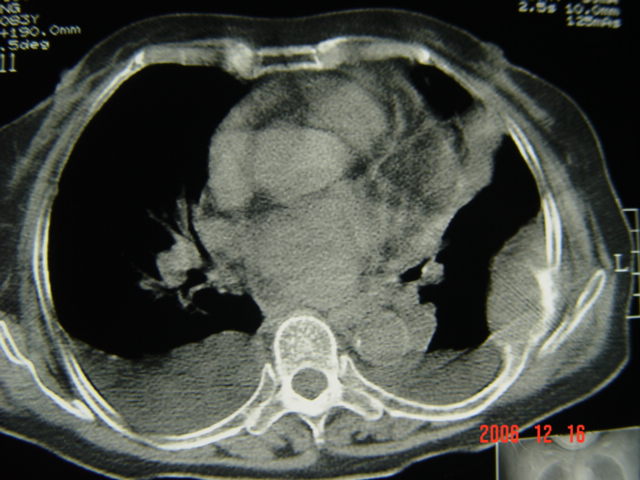

标题: CT5663:女、83岁,轻微咳嗽、左下胸痛。 [打印本页]

标题: CT5663:女、83岁,轻微咳嗽、左下胸痛。

考虑1左侧肋骨破坏考虑转移瘤。2左下肺部分肺不张或实变,左肺舌段片团影考虑肺癌可能性大[肺梗塞--往往有明显的胸痛,呼吸急促或困难等表现]。3双侧肺淤血及双侧胸腔积液考虑心功能不全所致可能性大

不要考虑的过于复杂,就是个肺癌,肋骨转移,隆突下淋巴结肿大,双胸腔积液

左肺舌段片团影考虑肺癌可能性大

左下肺部分肺不张

左第8肋骨转移瘤